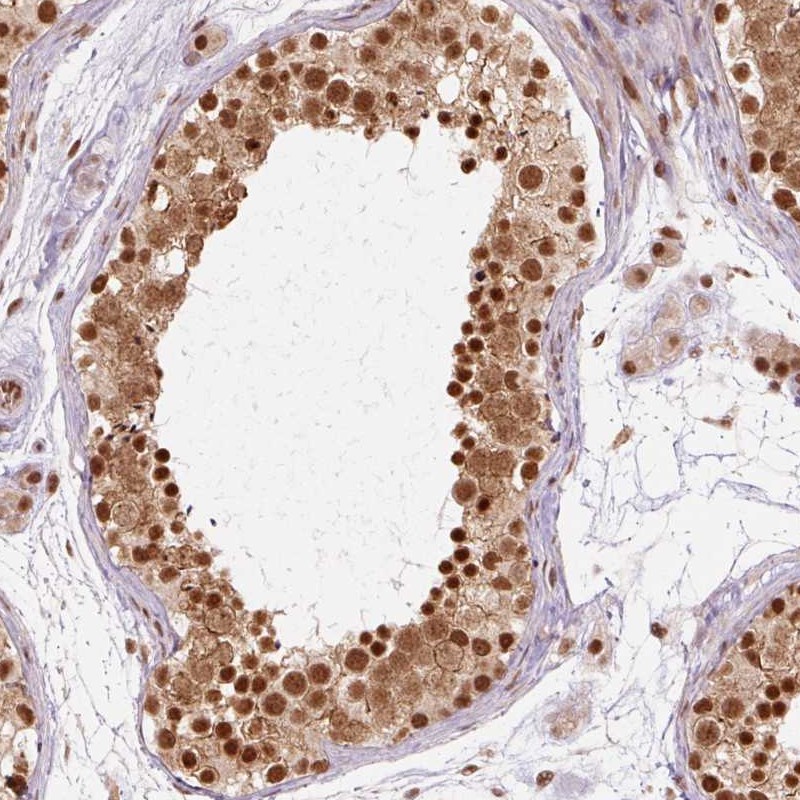

Immunohistochemical staining of human testis shows strong nuclear and cytoplasmic positivity in cells in seminiferus ducts.